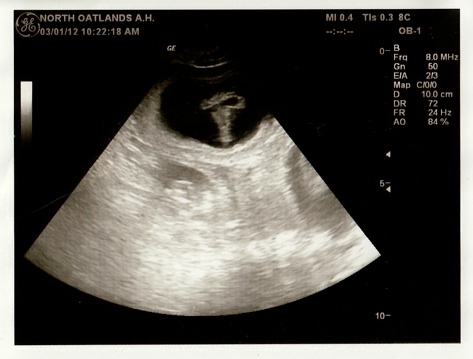

While initial attempts at breedings are not always successful, the breeding of Irish (the dam - Ch. Vanderbilt’s Stroke of Luck) and Harry (the sire - GCH. Mystic Oz’s Prince Harry) was productive the first time around.  An ultrasound thirty days later confirmed at least seven puppies.  On the next day Jan ordered a whelping box and assorted other gear to help ensure that Irish had a successful pregnancy and the puppies got off to a healthy start.  A bedroom was rearranged to accommodate the whelping “box,” the deck was secured and power-washed to give the puppies safe outdoor play space after they reach three weeks of age.  Another friend and PVSC member, Karla, loaned Jan a portable carrier for her SUV to transport the puppies (veterinarian visits).  Experienced breeders provided invaluable advice throughout this period to help Jan prepare for and conduct a successful whelping.

3/1:      sonogram